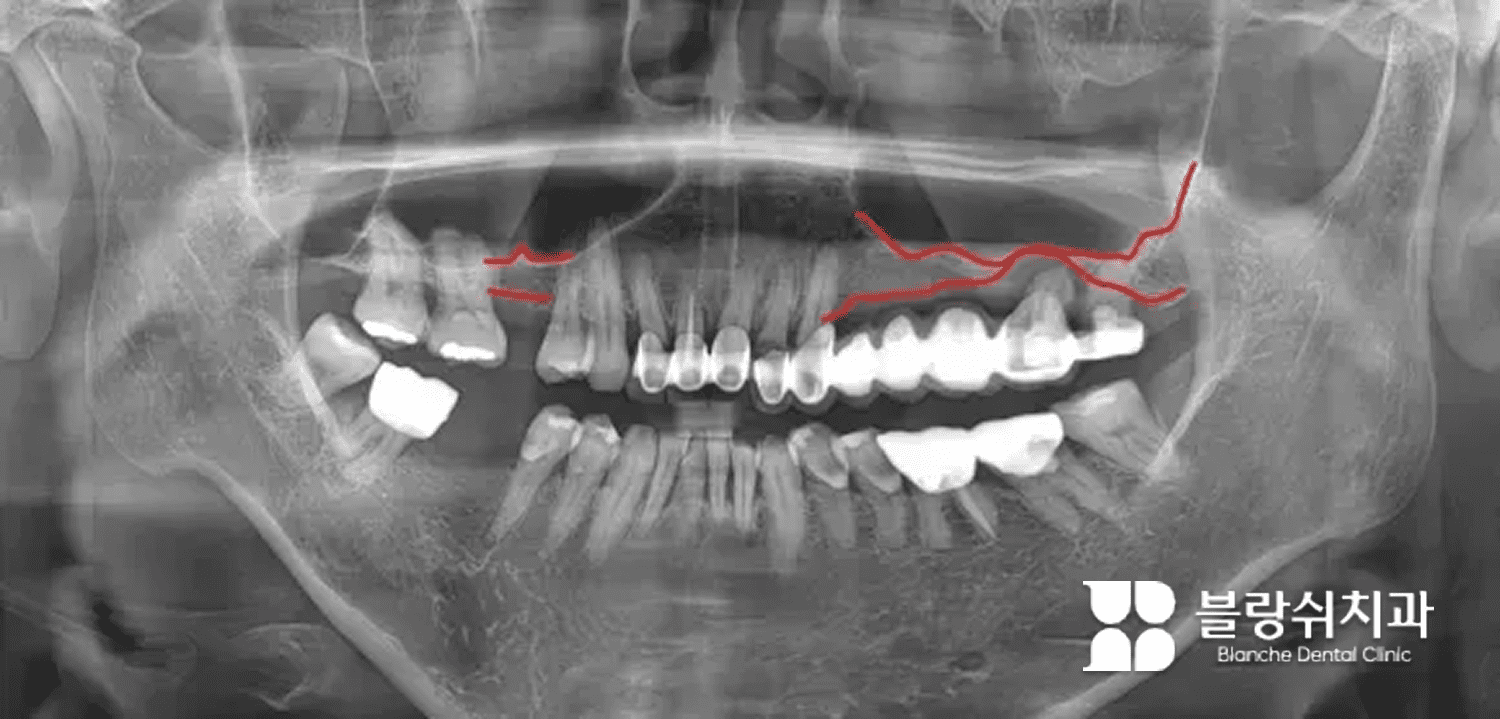

(1) 심각한 치주염으로 뼈가 녹은 경우

진료실에서 흔히 폭탄 맞은 자리라고 표현하는 케이스가 있어요. 치주염이 너무 심해 치아가 흔들리고, 엑스레이를 보면 치아가 뼈에 박혀 있는 게 아니라 공중에 떠 있는 것처럼 보이는 경우입니다.

이런 케이스를 많이 보다 보면 패턴이 보입니다. 치주염이 심했던 자리는 아무리 기다려도 뼈가 충분히 차오르지 않아요. 발치 자리가 지름 1cm 이상 싱크홀처럼 크게 비는 경우가 흔하고, 기다리면 오히려 결손이 더 커지기도 합니다.

그래서 이런 케이스는 발치 후 바로 뼈이식을 해주는 것이 효과적입니다. 이때 뼈이식은 ‘조금 더 튼튼하게’ 수준이 아니라, 임플란트를 가능하게 만드는 필수 기초 공사입니다. 오히려 결손이 명확해서 수술 목표가 분명하고, 원칙대로 진행하면 예후가 좋은 편이에요.

뼈이식 후에는 이렇게 엑스레이로 확인할 수 있습니다. 이식 재료는 뼈처럼 하얗게보이며, 상악동 거상술 부위는 동그랗고 하얗게 나타납니다.